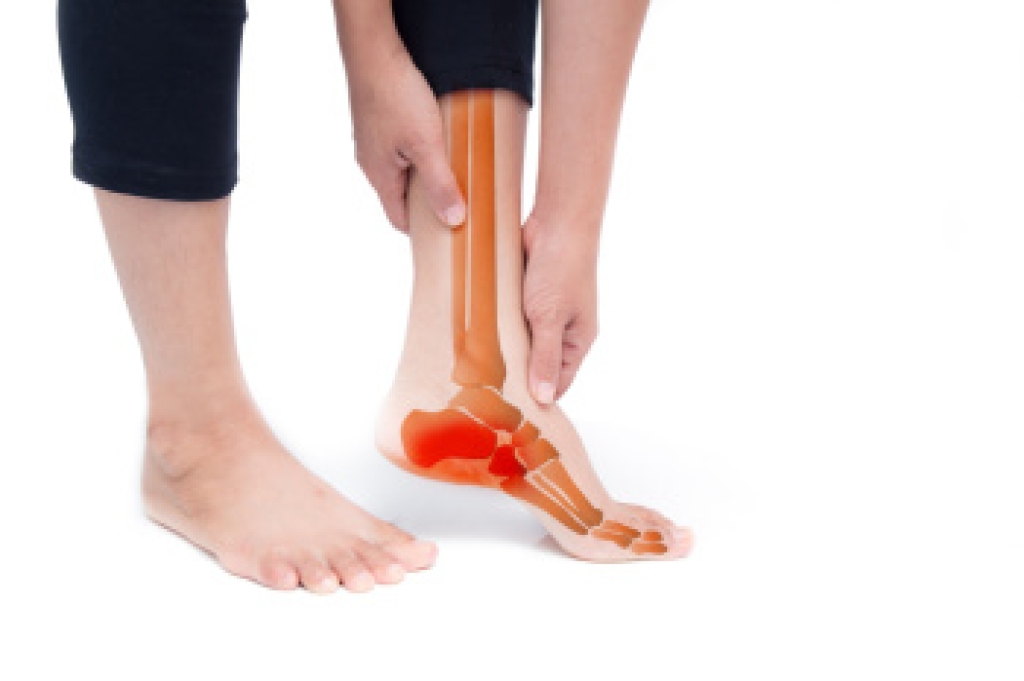

Plantar fasciitis is caused by inflammation of the plantar fascia, the thick band of tissue that supports the arch and connects the heel to the toes. It often leads to heel pain and stiffness, especially with first steps after rest. Risk factors include prolonged standing, repetitive strain, wearing poor footwear, flat feet, high arches, and excess body weight. Effective foot orthoses can help by supporting the arch, cushioning the heel, redistributing pressure, and reducing strain on the plantar fascia. A podiatrist can evaluate foot mechanics, confirm the diagnosis, and design custom foot orthoses as part of a comprehensive treatment plan. If heel pain is affecting comfort or mobility, it is suggested that you consult a podiatrist who can discuss the benefits of custom orthotics for relief and comfort.